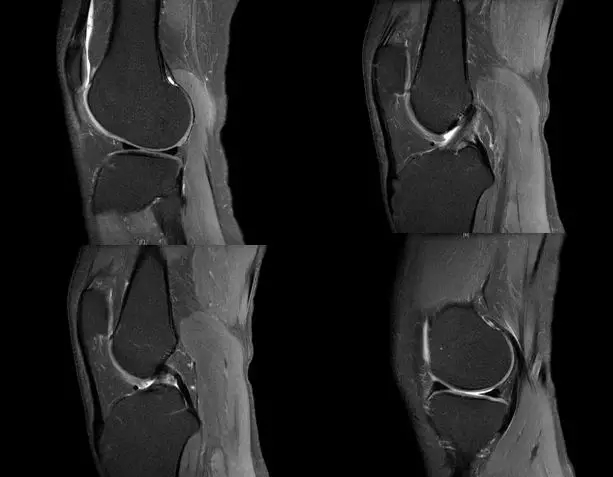

segond骨折

外髁骨擦伤(Kissing -sign)

陈旧性前交叉韧带断裂